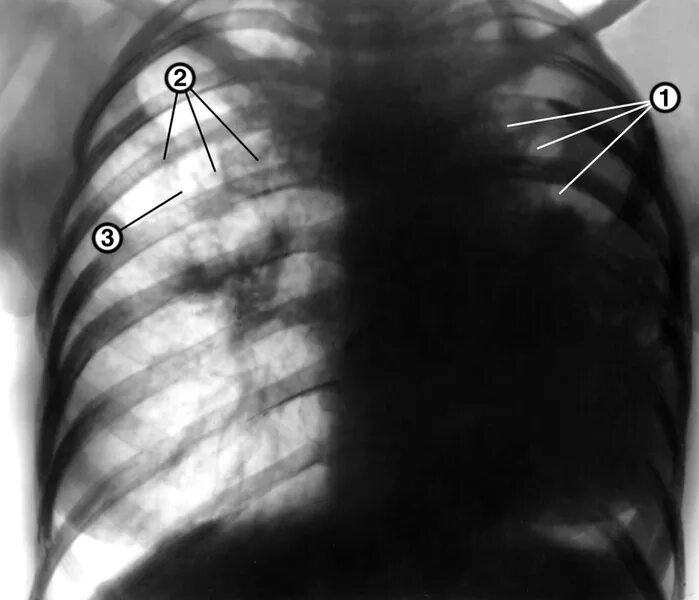

Фиброзное изменение левого легкого